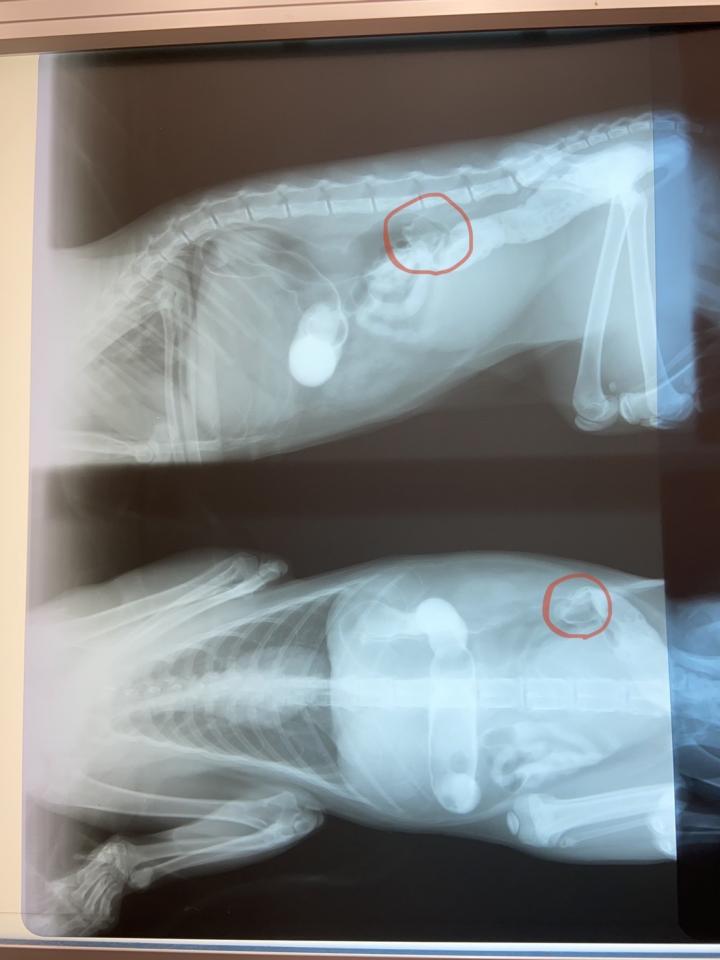

エコーとレントゲンへ。

ヤバい😱十二指腸までの間に何か詰まってる‼️

造影剤検査でも流れてない事を確認😣

入院させ、朝、術前に再度レントゲンとると、

なんと異物が大腸まで降りてきている、

このまま便から出るだろう、手術は回避との連絡